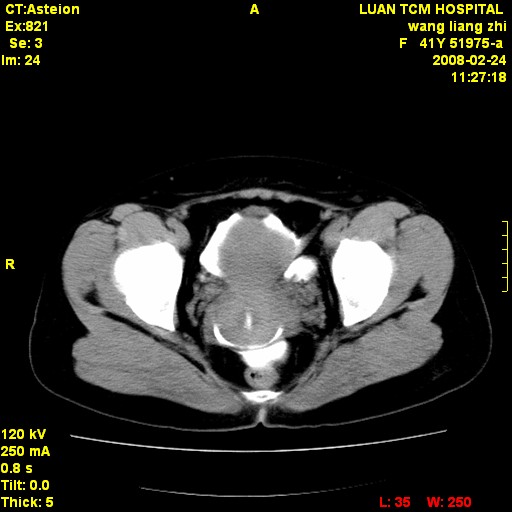

以下是引用dyqct在2009-8-23 16:17:00的发言:[br]考虑:1、造影剂进入腹腔、结肠旁沟、肝周;[br] 2、子宫明显增大(腺肌增生症?);[br] 3、膀胱显影是由于造影剂吸收后经肾分泌进入膀胱的;[br] 4、建议mri检查子宫。